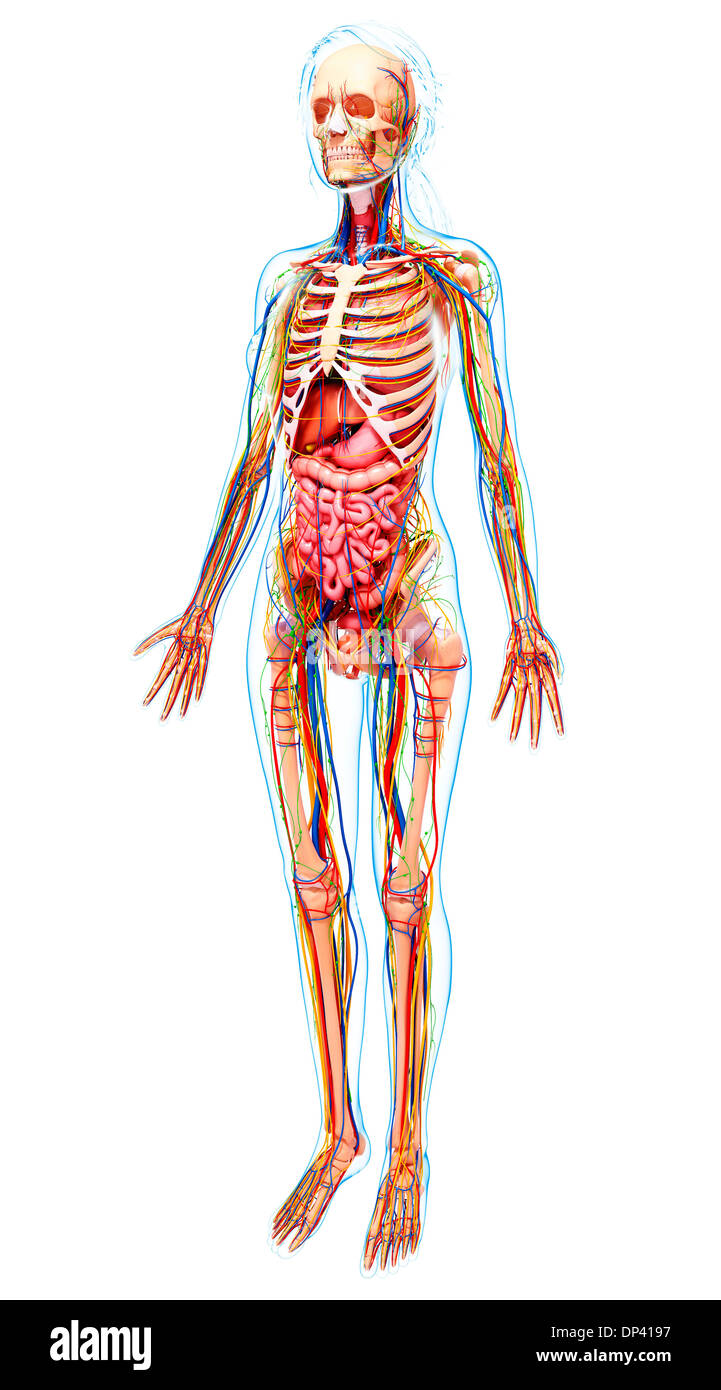

Human Anatomy, artwork Banque D'Imageshttps://www.alamyimages.fr/image-license-details/?v=1https://www.alamyimages.fr/human-anatomy-artwork-image65242387.html

Human Anatomy, artwork Banque D'Imageshttps://www.alamyimages.fr/image-license-details/?v=1https://www.alamyimages.fr/human-anatomy-artwork-image65242387.htmlRFDP4197–Human Anatomy, artwork